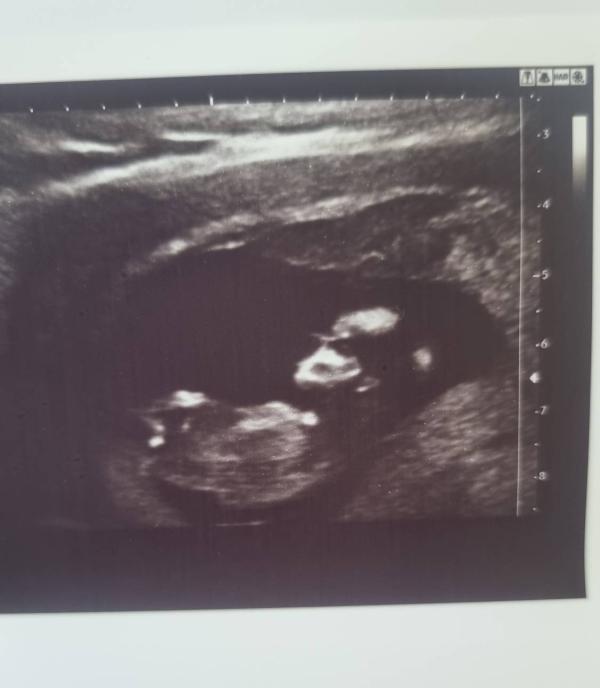

На первый скрининг я шла абсолютно спокойно, тк за несколько дней до этого, мы с мужем ходили на платное узи, где сказали , что у плода все значения в норме.

Там мы впервые увидели настоящего человечка внутри. 🫶 Было удивительно видеть, как крошка машет ручками, прыгает , но при этом совсем ничего не чувствовать.